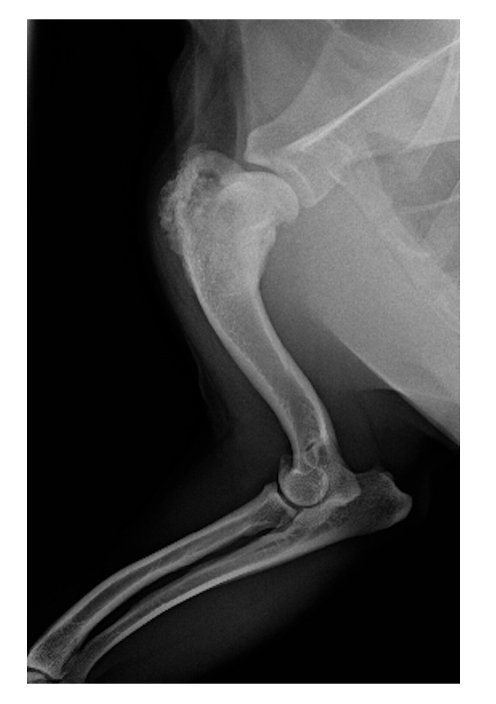

A 10yo, MN, 35kg mixed breed dog presents for right forelimb lameness. You get the following radiographs and cytology results. What is the recommended next step?

A. High-dose vincristine

B. Abdominal ultrasound

C. Chest radiographs

D. Forelimb amputation

A